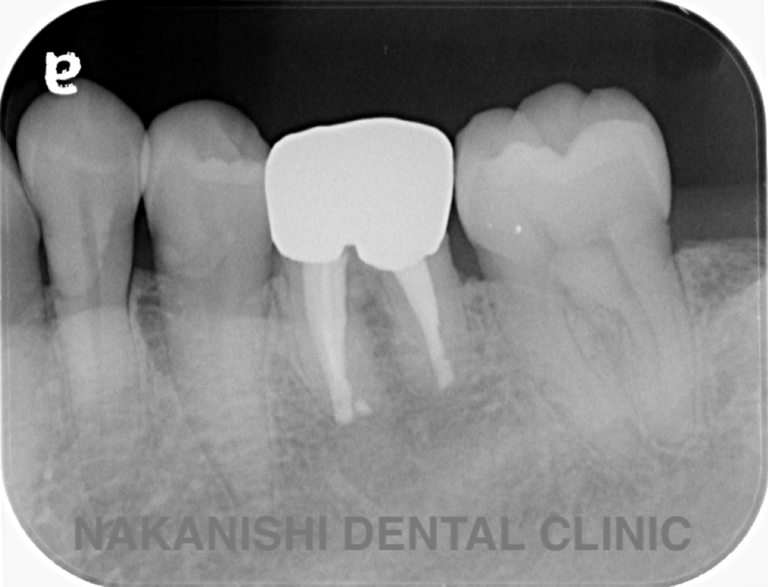

case 2.

治療前

治療後

| 主訴 | 左下歯ぐきの腫れ。 |

|---|---|

| 治療期間 | 約2か月 |

| 治療費 | 約1万5千円 |

| 治療内容 | ラバーダム、マイクロスコープ下にて根管治療を施術。 歯ぐきの腫れ、痛みや違和感が消失したため根管充填、支台築造(土台の製作)を行った。治療後の写真は矯正治療を行うことになったため仮歯を装着した状態。 |

| 治療のリスク | マイクロスコープやCTを使用し、可能な限り精密な根管治療を行っていますが、歯根の形態や病変の大きさ、過去の治療履歴などにより、治癒が得られない場合があります。また、治療後に再感染や歯根破折が生じることもあり、その場合は再治療や抜歯が必要となることがあります。 治療結果には個人差があり、すべての症例で同様の経過を保証するものではありません。 |